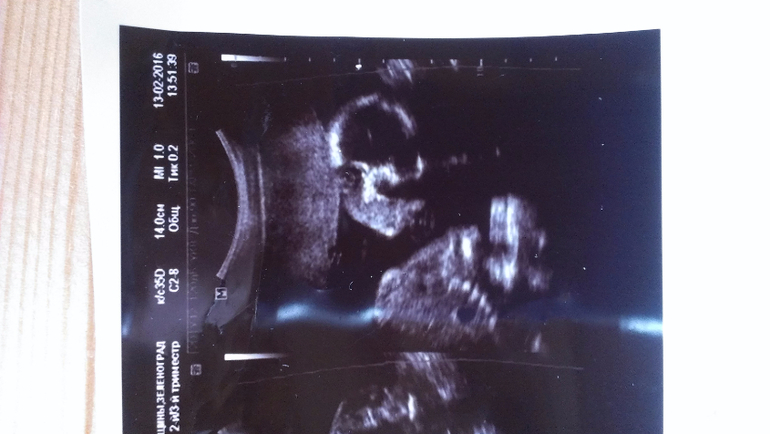

Внутриутробное развитие двойни/тройниНа узи в 20 недель уверенно сказали - два мальчика и на снимках так четко выделили, а неделю назад в другом центре врач как раз не очень уверенно, но предположила, что обе девочки...

На узи в 20 недель:

А у вас ну очень похожи на пацанов)

Вот мне тоже кажется, что, по крайней мере, с одним не могли ошибиться)) В любом случае, розовое (как и голубое) закупать не планировала, но люблю быть готовой.

Еще, все кто видел верхнее фото - сразу сказали, нос папин. Надеюсь, мальчику достался))